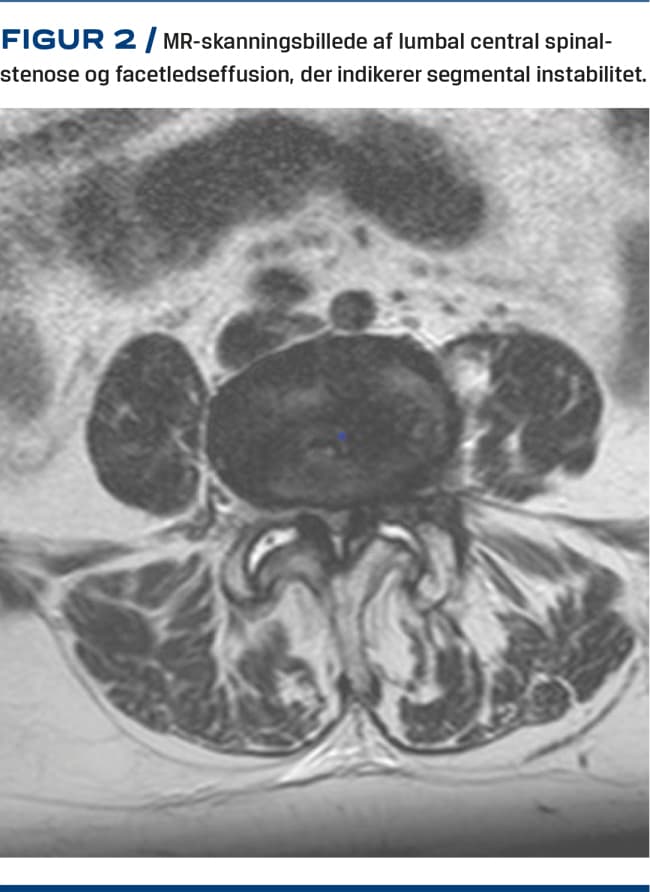

Med MR-skanning kan man som med CT påvise artroseforandringer i facetleddene. Dog undervurderes graden af artrose oftere ved MR-skanning end ved CT, men MR-skanning er bedre til visualisering af forandringer i de omkringliggende strukturer såsom påvirkning af de neurale strukturer, facetledscyster og -ansamlinger samt knogleødem (Figur 2). Baseret på MR-skanning har Fujiwara et al forslået en klassifikation fra grad 1, hvor der er normale forhold, og op til grad 4, hvor der forekommer udtalte osteofytter [19].